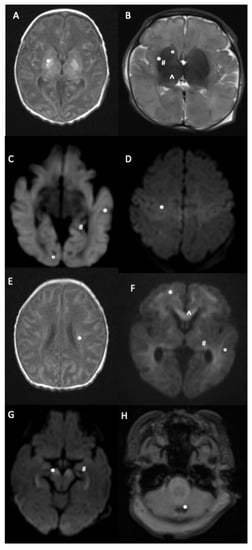

| BGT | 171/506 (33.8) | 157/466 (33.7) | 14/40 (35.0) |

| - Thalamus | 121 | 109 | 12 |

| - Globus pallidus | 93 | 84 | 9 |

| - Putamen | 85 | 78 | 7 |

| - Caudate nucleus | 59 | 52 | 7 |

| PLIC | 82/497 (16.5) | 72/456 (15.8) | 10/41 (24.4) |

| WM | 166/496 (33.5) | 148/456 (32.5) | 18/40 (45.0) |

| Cortex | 128/500 (25.6) | 114/459 (24.8) | 14/41 (34.2) |

| CC | 63/460 (13.7) | 56/422 (13.3) | 7/38 (18.4) |

| Brainstem | 44/501 (8.8) | 39/461 (8.5) | 5/40 (12.5) |

| Cerebellum | 24/491 (4.9) | 23/450 (5.1) | 1/41 (2.4) |